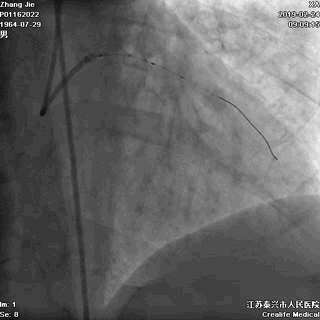

冠状动脉左主干完全闭塞,血流完全中断

冠状动脉造影:冠状动脉左主干急性闭塞(见上面右图)。至此,患者“左主干急性闭塞”诊断明确。遇上左主干急性闭塞患者,术者该如何施救才能让患者存活下来呢?